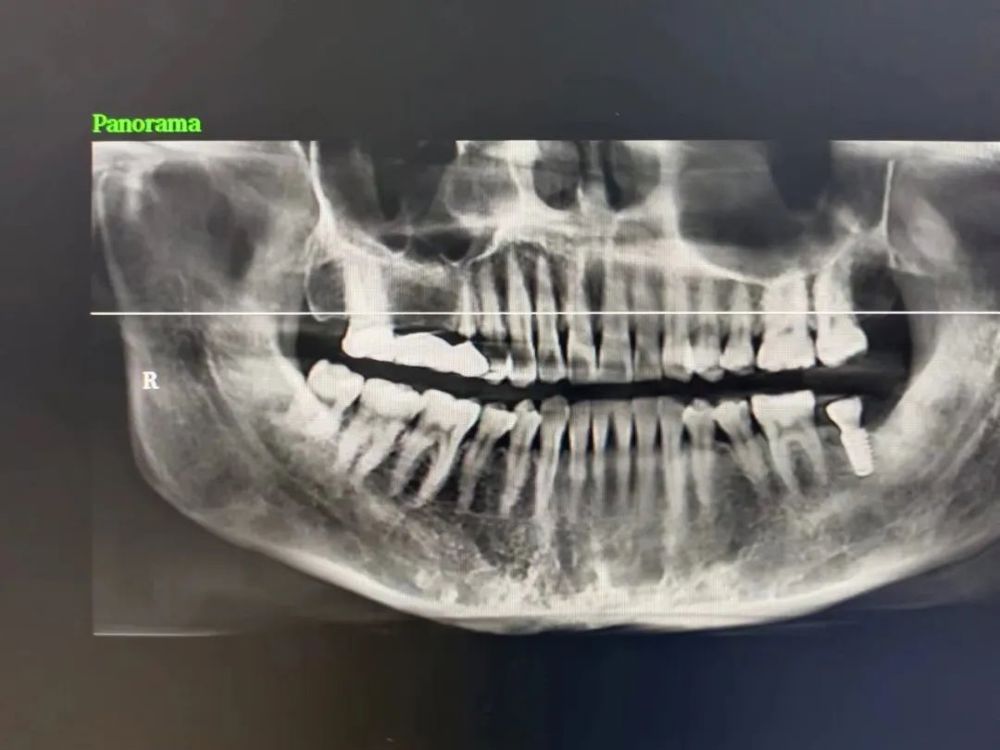

三、種植牙技術

目前,社會上很多人被牙齒缺失所困擾,牙齒缺失不但影響人的咀(jǔ)嚼和語言功能,對於人的麵部美觀也是一種(zhǒng)影響,甚(shèn)至有些人因缺失牙齒而不願意張口說話,種植牙被譽(yù)為人類“第三副牙齒”,因其舒(shū)適、美觀、功能好而被缺牙患者追捧。經衛建委批準,我院(yuàn)於2023年3月18日正式開展種植牙技術,開展當天門診手術7例共計14顆植體,術後1天回訪患者表示無紅(hóng)腫、無疼痛症狀,術後7天回(huí)訪一切良好無異常,術後10天拆線創口愈合良好,自(zì)開展口腔種植手術以(yǐ)來(lái),有(yǒu)許多患者紛紛(fēn)到科裏(lǐ)進行相關谘詢和檢查,更是不斷有患者預約意向種植,我院嚴格按照江西省(shěng)醫療保障局、江西省衛生(shēng)健康(kāng)委員會關(guān)於公布實施口腔種植類醫(yī)療服務價格有關事項的通知—贛醫(yī)保字《2023》3號文件執行操作,在(zài)手術診療中,嚴(yán)格操作流程,減少感染風險。我院口(kǒu)腔種植技術的成功和發(fā)展,不僅完(wán)善了傳(chuán)統(tǒng)牙(yá)齒修複技術的不足,而且在功能與美觀上給了人(rén)們嶄新的體驗,我(wǒ)院(yuàn)致力於提供一站式口(kǒu)腔種植診療(liáo)服務,必將為本縣及周邊缺失牙患者找回(huí)美麗、自信的微(wēi)笑。

案例(lì)二

種植前 種植後